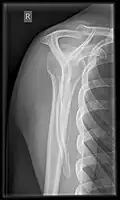

Shoulders

_X-ray_of_a_normal_shoulder.jpg)

These include:

- AP-projection 40° posterior oblique after Grashey

The body has to be rotated about 30 to 45 degrees towards the shoulder to be imaged, and the standing or sitting patient lets the arm hang. This method reveals the joint gap and the vertical alignment towards the socket.[17]

- Transaxillary projection

The arm should be abducted 80 to 100 degrees. This method reveals:[17]

- The horizontal alignment of the humerus head in respect to the socket, and the lateral clavicle in respect to the acromion.

- Lesions of the anterior and posterior socket border or of the tuberculum minus.

- The eventual non-closure of the acromial apophysis.

- The coraco-humeral interval

- Y-projection

The lateral contour of the shoulder should be positioned in front of the film in a way that the longitudinal axis of the scapula continues parallel to the path of the rays. This method reveals:[17]

- The horizontal centralization of the humerus head and socket.

- The osseous margins of the coraco-acromial arch and hence the supraspinatus outlet canal.

- The shape of the acromion

This projection has a low tolerance for errors and accordingly needs proper execution.[17] The Y-projection can be traced back to Wijnblath's 1933 published cavitas-en-face projection.[18]

In the UK, the standard projections of the shoulder are AP and Lateral Scapula or Axillary Projection.[15]